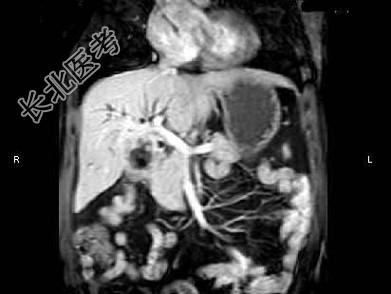

- 单项选择题根据所提供的图像,最可能的诊断是 ( )

A、胆囊癌

B、胆囊结石

C、胆囊息肉

D、胆囊炎

E、以上都不是